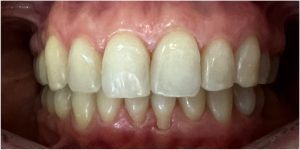

Pod kierownictwem lek. stom. Michała Badowskiego po wnikliwej analizie została przeprowadzona korekta dziąseł i pozbycie się nieestetycznych koron na podbudowie metalowej, eliminując tym samym nawracające stany zapalne dziąseł.

Następnie została wykonana wizualizacja nowego uśmiechu, idealnie dopasowana do twarzy Pacjentki. Po jej akceptacji, przygotowaliśmy komplet koron i licówek pełnoceramicznych na górne i dolne zęby.

Całe leczenie trwało zaledwie 3 miesiące!

Dzięki współpracy lek. stom. Michała Badowskiego i techn. dent. Joanny Gancarz z laboratorium Dentalscan Pacjentka zachwyca pięknym uśmiechem!